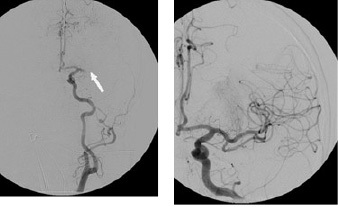

Figure 1. Neurovascular Imaging for an Acute Ischemic Stroke Patient Undergoing Evaluation for Endovascular Intervention (continued) |

![]() |

Cerebral angiogram (left) demonstrating MCA occlusion (arrow) and complete revascularization following IAT (right). |

MCA: middle cerebral artery; IAT: intra-arterial therapy Source: Lerario MP, Segal A. Acute ischemic stroke: Focus on reperfusion. Emerg Med Rep 2016;37:106-107. |

Case: An 84-year-old man with hypertension, coronary artery disease status post-bypass, and stenting presented to the emergency department with acute onset aphasia and right hemiparesis. The initial NIHSS was 12. Noncontrast head CT ruled out hemorrhage and found no early ischemic changes (ASPECTS 10). CTA demonstrated an occlusion of the proximal MCA. The patient was outside of the window for IV tPA. Groin puncture occurred within six hours of onset. The interventionalist achieved full recanalization with a single pass of a stent-retriever device. The patient was found to have atrial fibrillation as the cause of his stroke. He was discharged home with full strength and minor aphasia. |